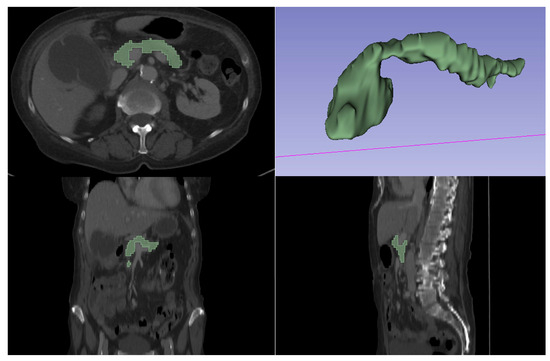

2.3. Automatic Segmentation, Feature Extraction and Selection and Statistical Analysis